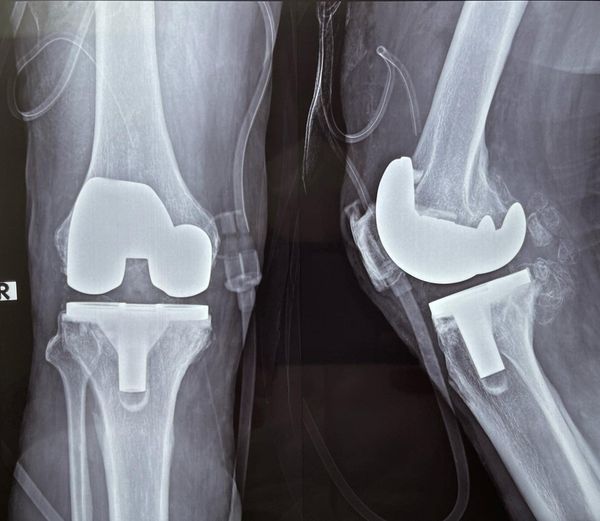

Some problems if ignored for fear or some other prejudice can cripple a person permanently, like this 65 yr old gentleman who can barely walk with this extremely deformed knee, correction of such a deformity can be challenging because of the inherent bone loss of nearly 15 mm that was discovered during surgery, however with the advent of swasthyasathi and other forms of medical insurances such surgeries are now can be done for free to give even people with less fortune a new breath of life. the total knee replacement knee deformity correction Monday surgery